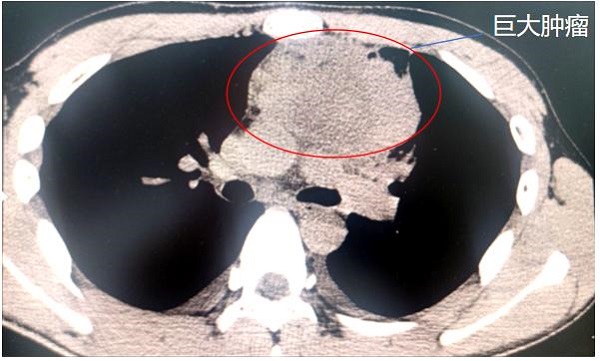

最終,在家人的陪伴下,林杰來到重醫附屬大學城醫院就診。CT檢查結果顯示,林杰的上縱隔頸胸交界處盤踞著直徑達10厘米的腫瘤,如同成年男性拳頭大小,并且緊貼心臟、主動脈弓分支及無名靜脈。

前上縱隔頸胸交界處巨大腫瘤。重醫附屬大學城醫院供圖